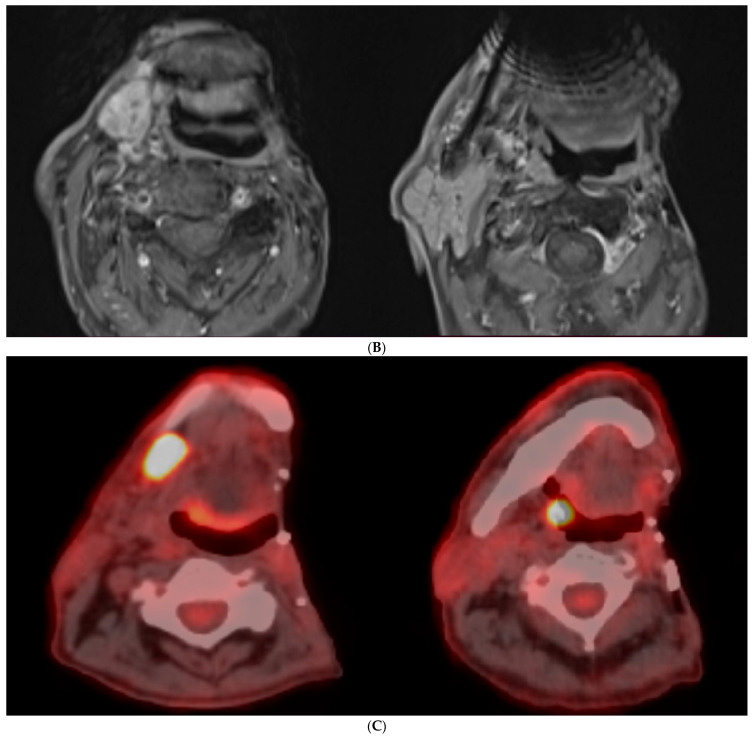

Materials and methods: A case of an 89-year-old man is reported, who initially underwent surgical and complementary treatment for neck squamous cell carcinoma of occult primary and later for tonsillar diffuse large B-cell non-Hodgkin lymphoma.

Results: The second primary was considered a recurrence in the neck of the original cancer of unknown primary, so a new surgical management was decided. The final pathology report described a diffuse large B-cell non-Hodgkin lymphoma.